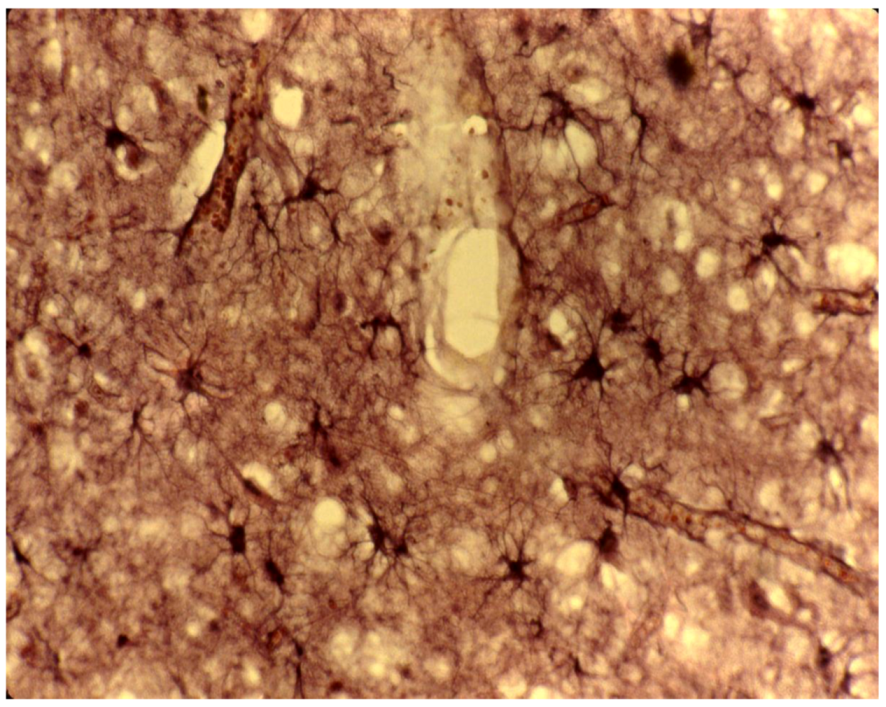

8. Neuropathology

- Biernat, W.; Liberski, P.P.; Guiroy, D.C.; Yanagihara, R.; Gajdusek, D.C. Proliferating cell nuclear antigen immunohistochemistry in astrocytes in experimental Creutzfeldt-Jakob disease and in human kuru, Creutzfeldt-Jakob disease and Gerstmann-Sträussler-Scheinker syndrome. Neurodegeneration 1995, 4, 195–201. [Google Scholar] [CrossRef]

- Liberski, P.P.; Sikorska, B.; Lindenbaum, S.; Goldfarb, L.G.; McLean, C.; Hainfellner, J.A.; Brown, P. Kuru: Genes, cannibals and neuropathology. J. Neuropathol. Exp. Neurol. 2012, 71, 92–103. [Google Scholar] [CrossRef]

- Hainfellner, J.; Liberski, P.P.; Guiroy, D.C.; Cervénaková, L.; Brown, P.; Gajdusek , D.C.; Budka, H. Pathology and immunohistochemistry of a kuru brain. Brain Pathol. 1997, 7, 547–554. [Google Scholar] [CrossRef]